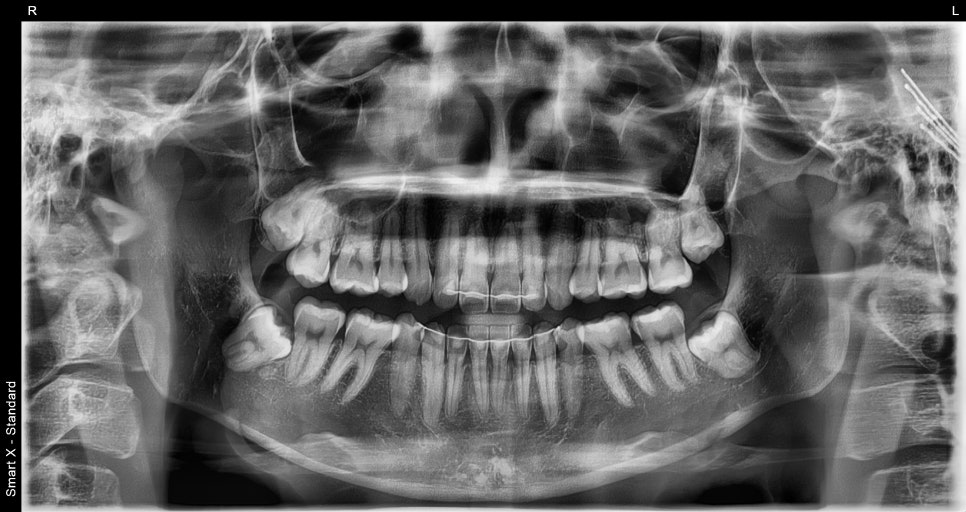

Through the initial consultation and digital analysis,

the following areas were selected for improvement:

The size and proportions of the front teeth (#13,12, 11, 21, 22,23)

The fine gaps between the teeth

The overall tooth tone and surface texture

Tooth reduction was limited to within 0.1–0.2 mm,

① Digital scan & design

– Precise data acquisition with an intraoral scanner → 3D design and simulation